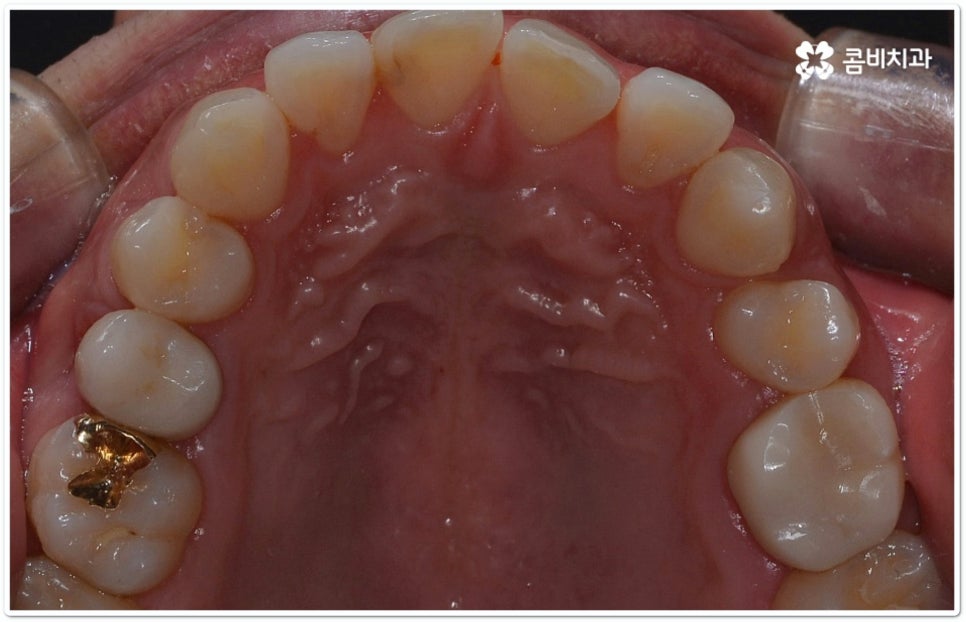

클리피씨교정 장치란 clippy-c 라는 단어 뜻에서 알 수 있듯이 클립이 달린 (clippy) 세라믹(ceramic) 브라켓 장치를 의미하고 있어요. 예전에 교정 장치에서 많이 쓰이던 방식은 고무줄 또는 미세철사를 이용하여 브라켓마다 각각 와이어를 묶어주는 것으로 날카롭게 잘린 철사 끝부분에 자칫 상처를 입을 수도 있고 한 달에 한 번 정도 치과에 내원하여 진행 상황에 따라 교정력을 조정하는 시간도 훨씬 더 많이 걸렸다고 할 수 있습니다.

이와는 다르게 클리피씨교정 장치는 자가결찰방식이라고 해서 각 브라켓에 여닫을 수 있는 특수한 클립(뚜껑)이 달려 있어 전체 와이어를 통과시켜 잡아주는 방식을 이용하기 때문에 겉면이 매끄럽고 진료 시간도 짧아지며 마찰로 빠져나가는 교정력을 줄여주어 좀 더 효율적으로 치아를 이동시킨다고 할 수 있어요. 즉 보다 적은 힘으로 지속적이고 부드러운 치아 이동을 가능하게 하므로 언급했던 것처럼 개인차가 있지만 전체 기간을 약 6개월 정도 단축시키고 치아가 이동할 때 느낄 수 있는 초기 통증도 감소시켜 줄 수 있는 거예요. 또한 치아 색상과 비슷한 세라믹 재질을 이용하기 때문에 음식을 먹거나 대화를 하는 등 입을 벌렸을 때 보일 수 있는 교정 장치가 그렇게 크게 눈에 띄지 않아 심미적으로도 뛰어나다는 장점을 가지고 있습니다.

클리피씨교정 장치 외에도 다양한 장치들이 있으며 각각의 장단점이 있으므로 이에 대해서 의료진과 충분히 상담해 보시고 자신의 상황에 맞는 장치를 신중하게 선택해 보시면 좋을 거예요. 특히 말씀드렸던 것처럼 장치를 선택하는 데 있어서는 환자분들께서 중요하게 생각하시는 우선 순위를 반영할 수 있는 여지가 있기 때문에 이에 대해서 담당의 선생님께 말씀을 드리고 의견을 나눠보셔야 교정 과정 중에 신경 쓰일 수 있는 부분에 대해서 부담을 덜 수 있어요.